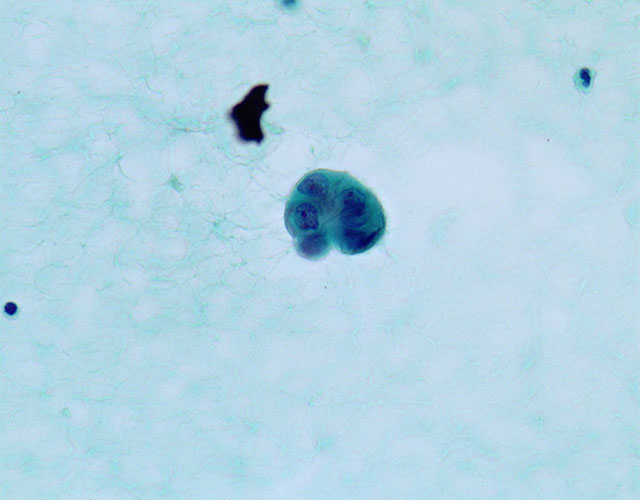

異型細胞の小集塊